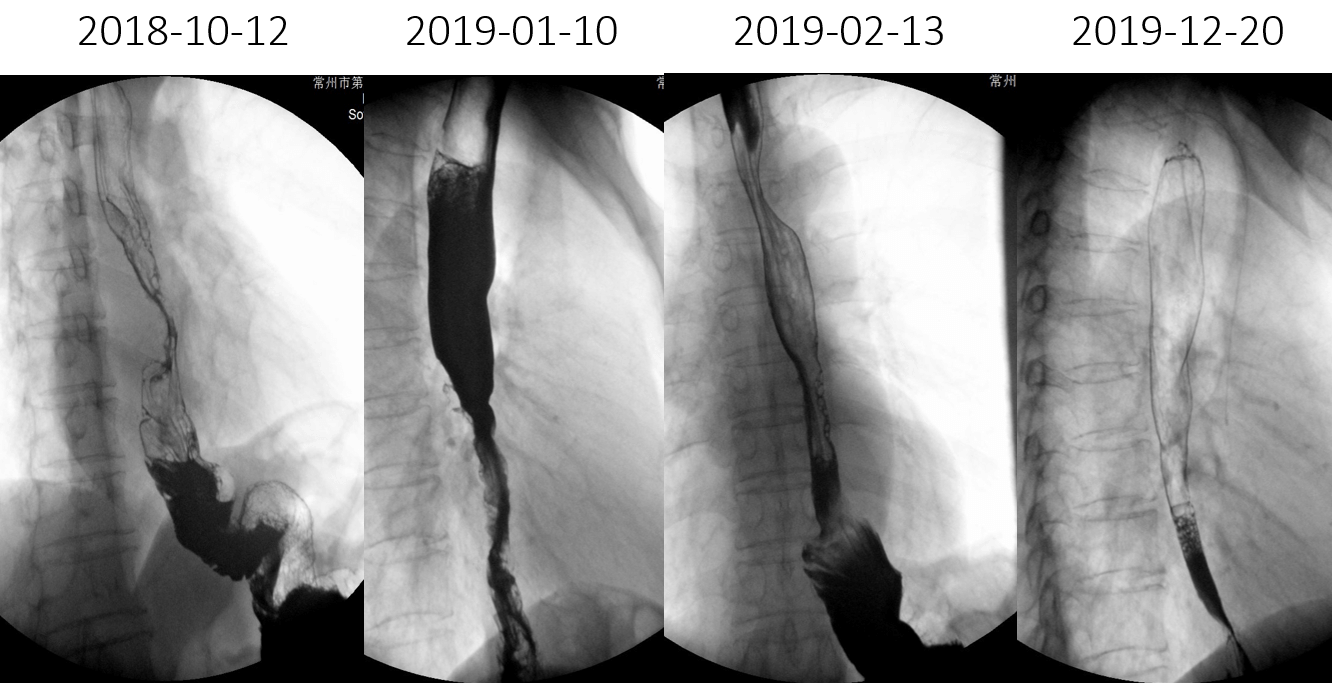

GI(2018-10-12):1、结合病史,考虑为食管中下段MT。2、胃术后改变

(1)2019-01-08进食梗咽症状加重入院,2019-01-14–02-22开始食管及吻合口放疗,以定位CT所示食管肿瘤为GTV,GTV及其上方75px食管外放12.5px为PTV, 95%PTV=5600cGy/28f,吻合口向下50px小肠外放12.5px为PTV1,95%PTV1=5000cGy/25f

(9)12-19复查CT:腹腔淋巴结较09-26日缩小,3疗程“雷替曲塞 durvalumab“治疗评估达PR。